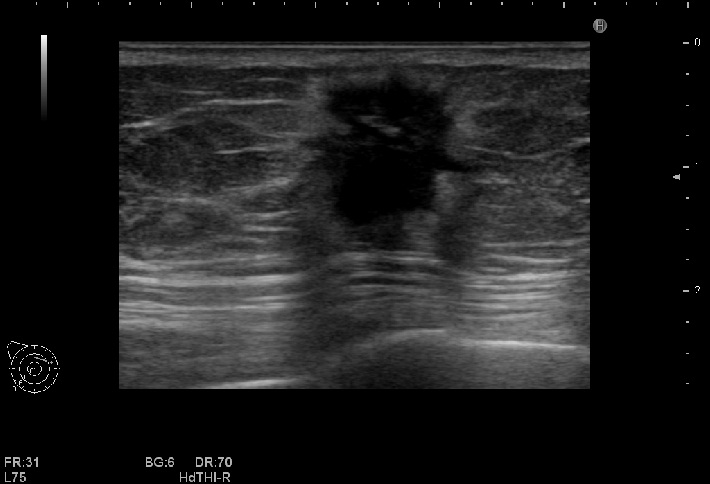

乳腺超音波検査

乳腺内の腫瘤や、乳腺構造の変化などを観察します。腋窩のリンパ節もチェックします。乳腺検査は女性技師が担当します。

必要に応じて、外科のドクターによる超音波ガイド下針生検を行っています。

乳癌のエコー像